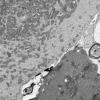

BASIC PROCESSES

Neuroaxonal dystrophy (2)